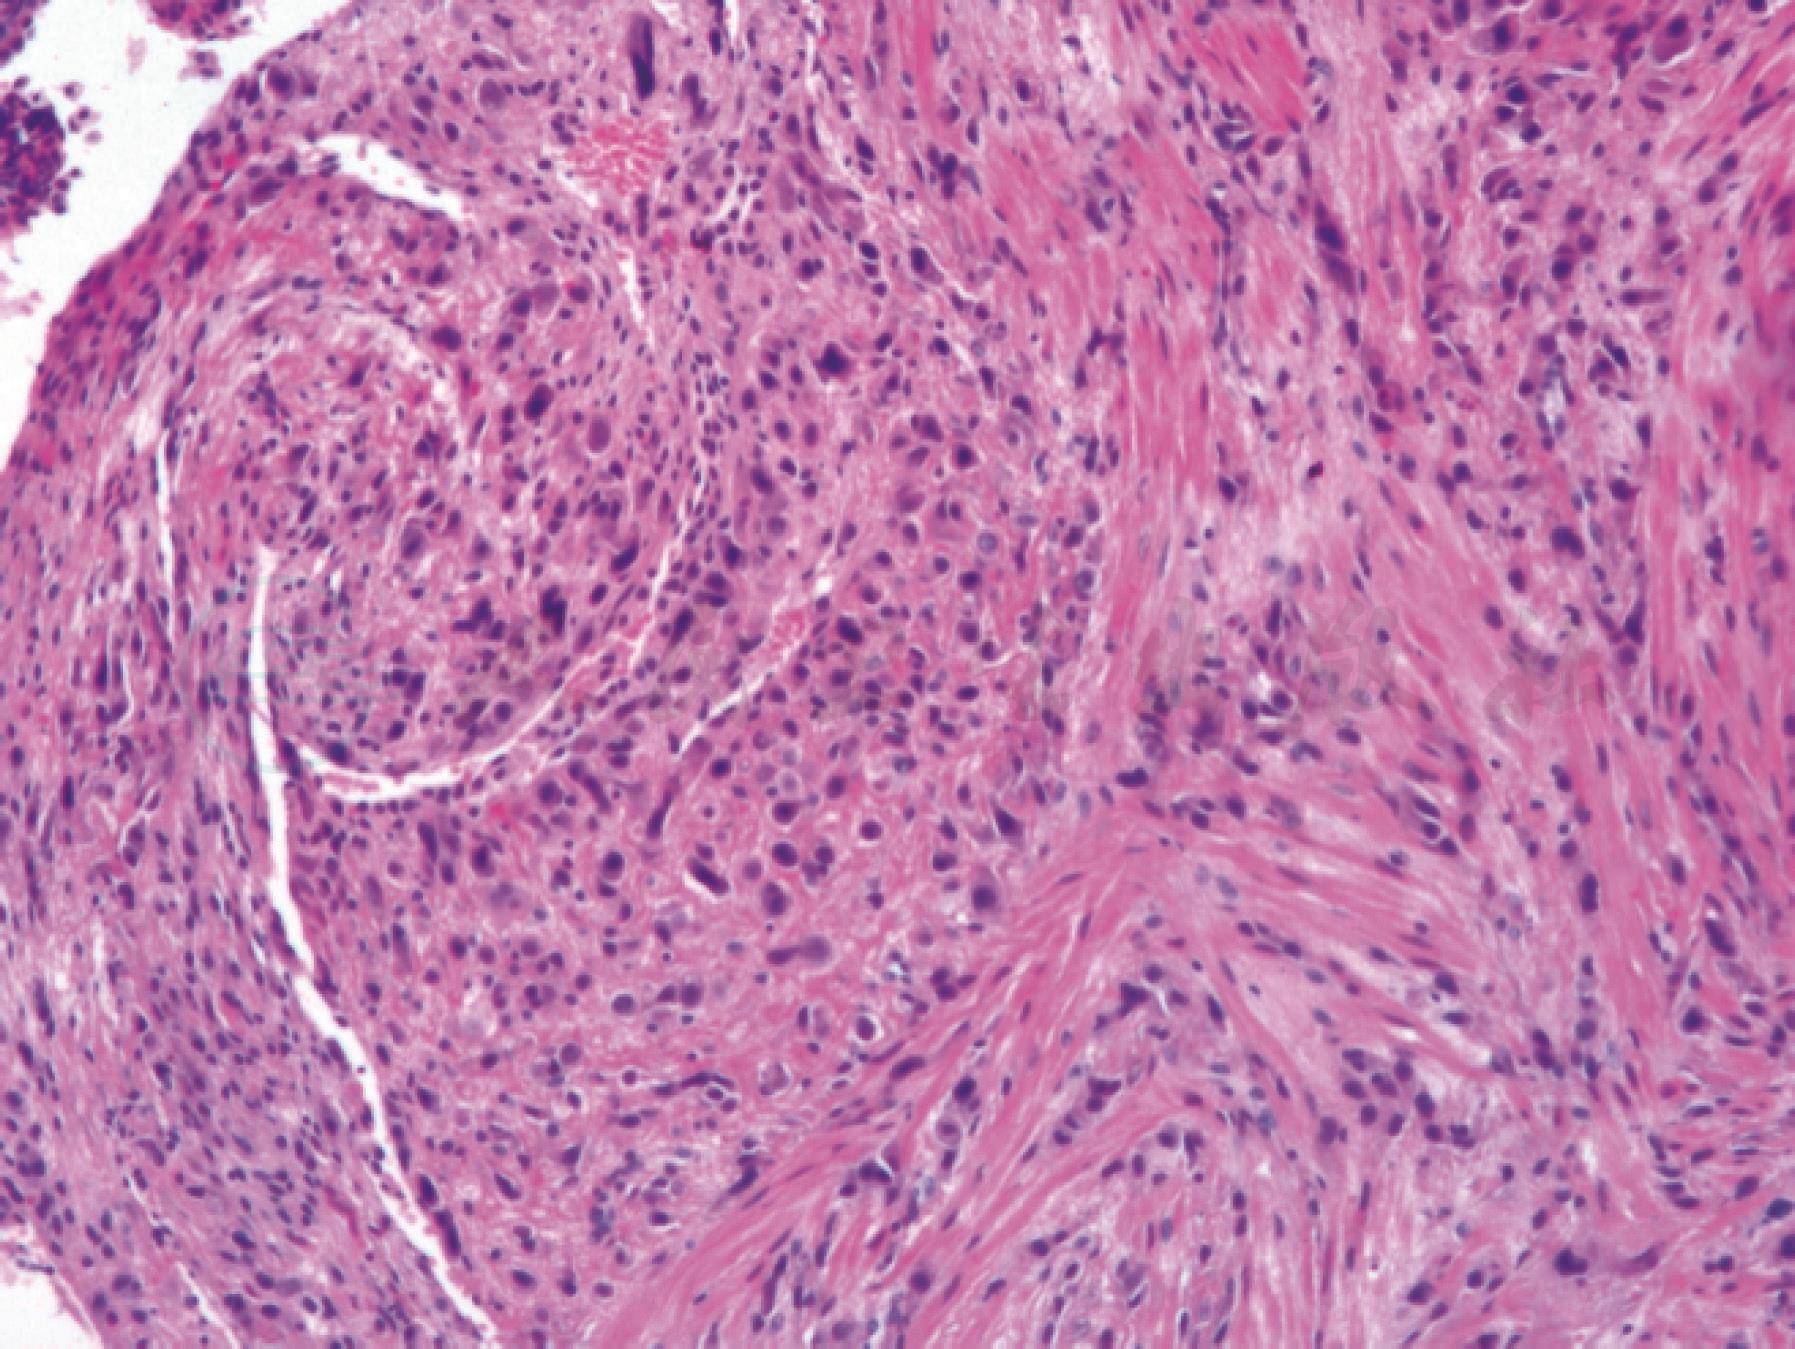

显微镜下:子宫内膜及浅肌层的中间型滋养细胞数量增加,中间滋养细胞呈单个、小巢状、小片状排列,可进入子宫内膜腺体及平滑肌纤维,但不破坏肌纤维。周围常伴有胎盘绒毛(图1)。

图1胎盘部位过度反应

子宫浅肌层中种植部位中间型滋养细胞数量增加,细胞呈单个、小巢状排列。